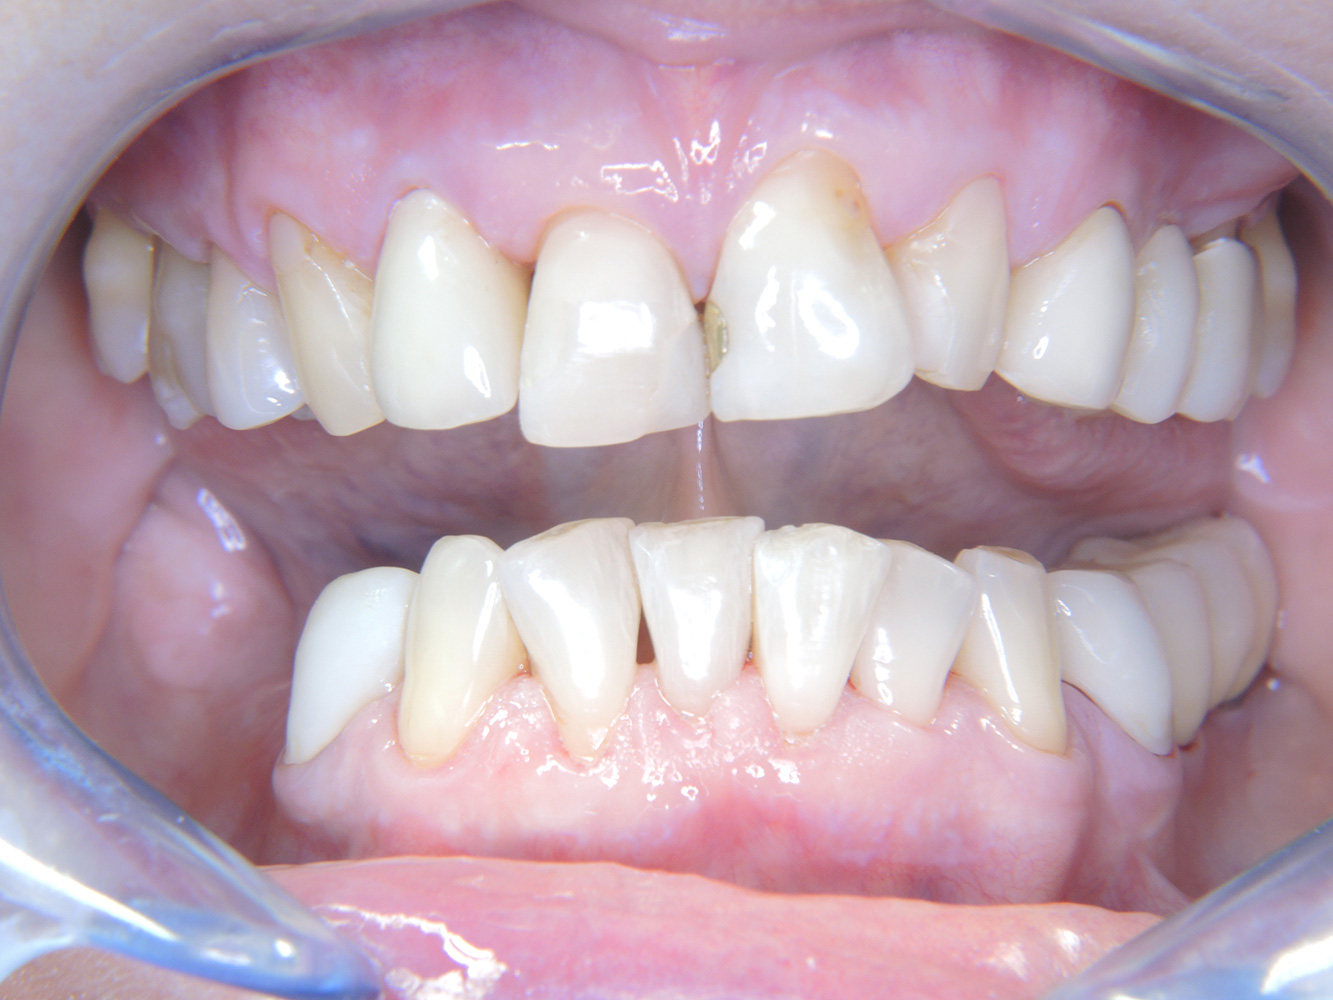

Die 68-jährige Patientin hat keine zahnmedizinisch relevanten allgemeingesundheitlichen Vorerkrankungen oder Medikation, auch aus dem Lebensstil ergibt sich kein besonderes Risiko. Die Patientin hat zwei Implantate (3. Quadrant, seit fünf Jahren) sowie eine parodontale Vorerkrankung (Parodontitis Stadium IV, Grad B) mit Zahnverlust. Derzeit zeigen sich stabile parodontale Verhältnisse. Für die Prophylaxesitzung ergeben sich vier Empfehlungen in den Bereichen Anamnese/Befund, Motivation/Instruktion, der Wahl der geeigneten Instrumente und für Resümee/Folgetermin.

Trotz der stabilen Verhältnisse sollten auch bei dieser Patientin die Motivation/Instruktion nicht vernachlässigt werden. Besonderes Augenmerk gilt dem Erlernen der richtigen Implantatpflege. Gerade hier kann eine gute häusliche Pflege einen wichtigen Anteil an der langfristigen Stabilisierung der Mund- und Implantatgesundheit haben.

In der Instrumentierung gilt im Bereich der Implantate eine besondere Vorgehensweise. Zum Erhalt der Implantatoberfläche bei gleichzeitig effektiver Reinigung ist die Wahl passender Pulver und Instrumente ausschlaggebend, wie etwa der gezielte Einsatz von Pulverstrahlgeräten mit speziellen Paro-Spitzen. Die Wahl des geeigneten Pulvers kann bedarfs- und risikogerecht erfolgen, beispielsweise kann neben dem passenden Abrasionsgrad auch auf diätische Anforderungen (u. a. zuckerfrei, salzarm) eingegangen werden.

Aufgrund der Implantatsituation mit parodontaler Vorerkrankung hat die Patientin ein Entstehungsrisiko für eine Periimplantitis – empfohlen wird eine Wiedervorstellung im Intervall von drei bis vier Monaten.